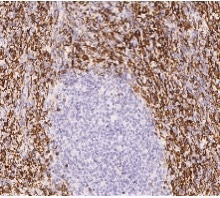

Anti-CD16b antibody. Mouse monoclonal. Cat#: 11046-MM07.

Immunochemical staining of human CD16b in human spleen. Image Credit: Sino Biological Inc.